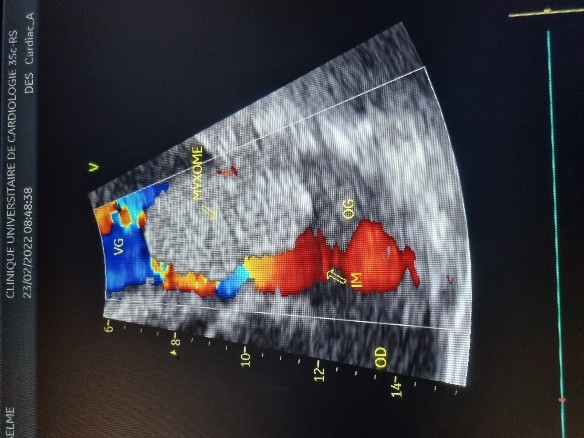

L’électrocardiogramme notait un rythme sinusal régulier avec une fréquence cardiaque à 83 bpm, des anomalies de la repolarisation en antéro septal à type d’ondes T biphasiques et en inférieur à type d’ondes T négatives asymétriques. La biologie était normale. L’échocardiographie (transthoracique et transœsophagienne) retrouvait les mêmes caractéristiques avec une masse appendue à la face atriale de la grande valve mitrale, obstruant partiellement l’orifice mitral et mesurant 49mm ×27 mm. Elle faisait protrusion dans le ventricule gauche en diastole (Figures 5 et 6). Cette masse était évocatrice d’un myxome de l’oreillette gauche. Le ventricule gauche n’était pas dilaté (DTDVG= 46mm), avec une fraction d’éjection systolique à 74% au Simpson biplan. Les pressions de remplissage du ventricule gauche étaient élevées. L’oreillette gauche était dilatée (VOG= 43mL/m²). Les cavités droites n’étaient pas dilatées. La fonction ventriculaire droite était normale (TAPSE= 24mm). On notait une hypertension pulmonaire avec PAPS =75mmHg, VmaxIT= 4,18 m/s. La veine cave inférieure était fine et compliante.

Figure 5 (a, b et c): Echocardiographie transthoracique en mode bi dimensionnel montrant un large myxome de l’oreillette gauche appendu à la face atriale de la grande valve mitrale faisant protrusion dans le ventricule gauche en diastole vu en incidence apicale 4 cavités (a et b) et 2 cavités avec doppler couleur notifiant une insuffisance mitrale (c) chez un patient de 57 ans. (Cas clinique n° 3). VG= ventricule gauche ; OG= oreillette gauche ; OD= oreillette droite ; VD= ventricule droit

Figure 6: Echocardiographie transoesophagienne en bi dimensionnelle, incidence 4 cavités vue bi-commissurale montrant un myxome appendu à la face atriale de la grande valve mitrale et faisant protrusion dans le ventricule gauche en diastole (Cas clinique n°3). VG= ventricule gauche ; OG= oreillette gauche.